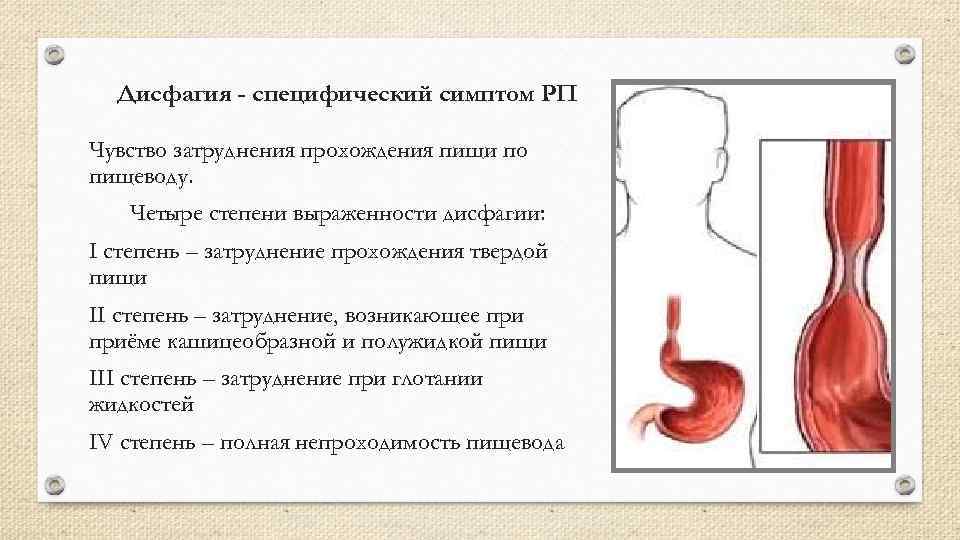

Дисфагия - специфический симптом РП Чувство затруднения прохождения пищи по пищеводу. Четыре степени выраженности дисфагии: I степень – затруднение прохождения твердой пищи II степень – затруднение, возникающее приёме кашицеобразной и полужидкой пищи III степень – затруднение при глотании жидкостей IV степень – полная непроходимость пищевода

Дисфагия - специфический симптом РП Чувство затруднения прохождения пищи по пищеводу. Четыре степени выраженности дисфагии: I степень – затруднение прохождения твердой пищи II степень – затруднение, возникающее приёме кашицеобразной и полужидкой пищи III степень – затруднение при глотании жидкостей IV степень – полная непроходимость пищевода